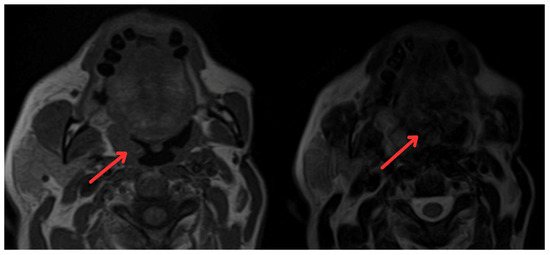

2. Case Report